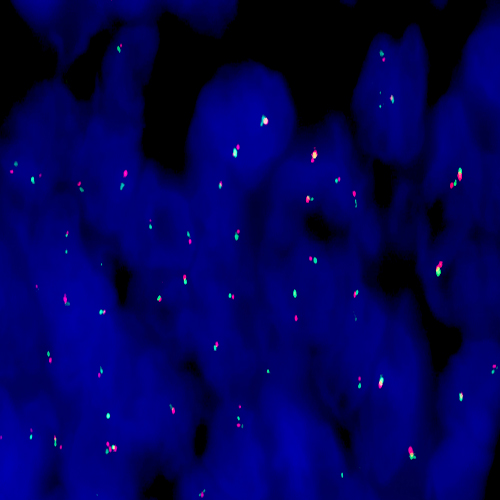

Human breast carcinoma: immunohistochemical staining for p120 Catenin antigen. Note membrane and cytoplasmic staining of malignant cells. p120 Catenin: clone EP66

p120 Catenin is a regulator of cell-cell adhesion, achieved through interaction with classical and Type II cadherins. Evidence also exists for a role in the regulation of cadherin availability on the cell surface. p120 Catenin also regulates actin dynamics, placing it as a potential master regulator of the cell motility/cell adhesion phenotypes.

Recent studies have suggested a tumor-suppression role for p120, with loss of p120 expression implicated in the development of a tumor microenvironment and induction of metastatic progression. The expression of p120 Catenin has been highlighted in early lobular breast neoplasias.